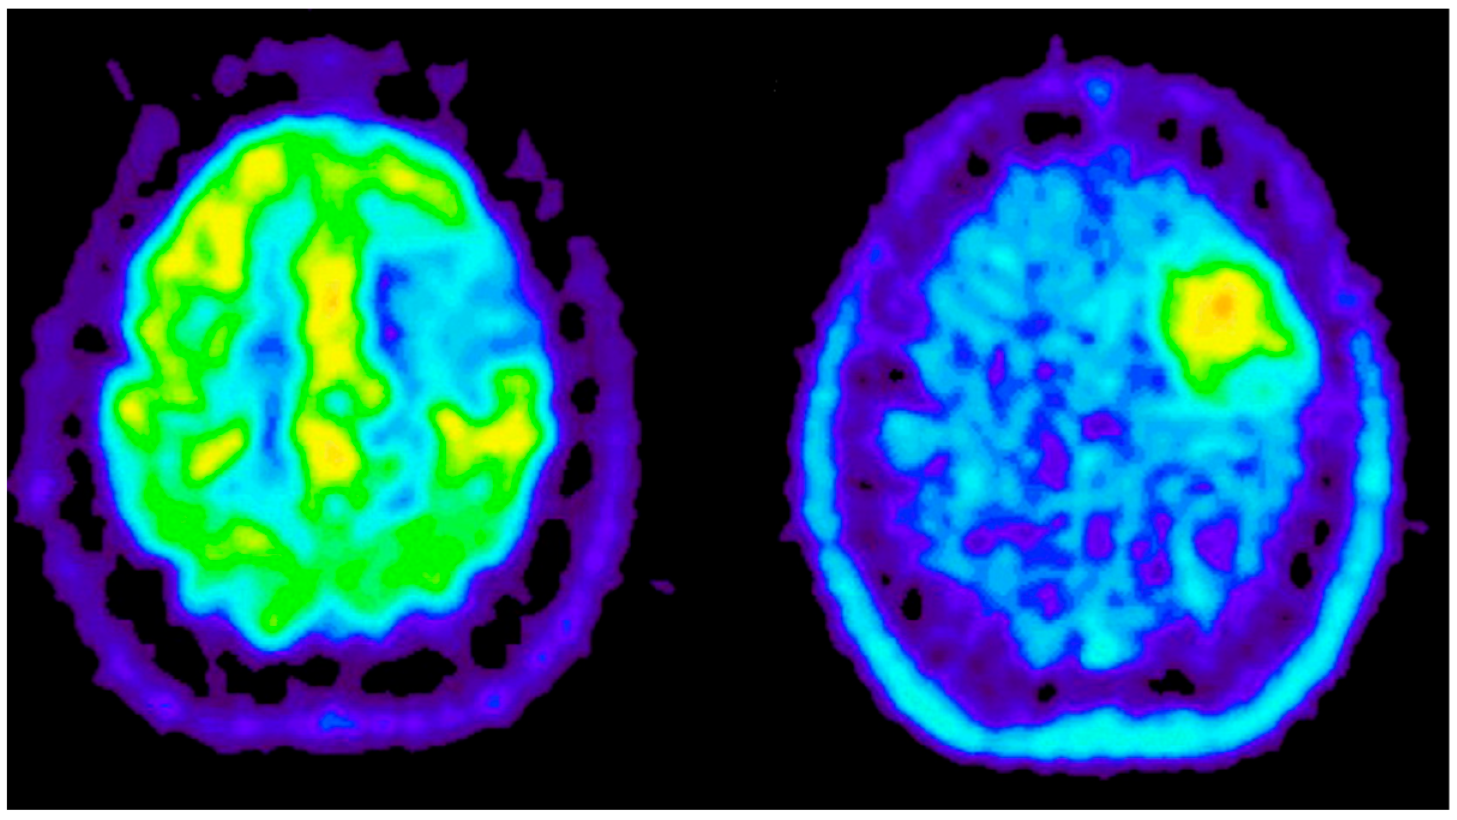

Appendix B.2.2. Positron Emission Tomography (PET)

- Torigian, E.A.; Huang, S.S.; Houseni, M.; Alavi, A. Functional imaging of cancer with emphasis on molecular techniques. CA Cancer J. Clin. 2007, 57, 206–224. [Google Scholar] [CrossRef] [PubMed]